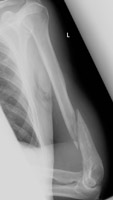

- Click on the image for a larger versionALateral radiograph of the humerus. There is a comminuted fracture of the shaft. Examining the image closely shows a permeative destructive process as well. This patient had lung cancer with other osseous metastases. This is a pathologic fracture.